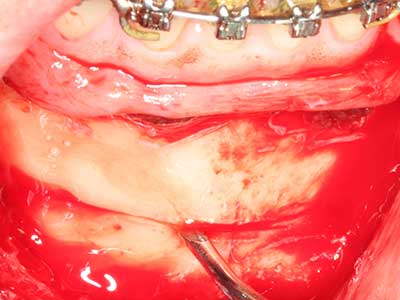

Piezo surgery has additional advantages when harvesting bone blocks. In addition to the high precision with osteotomy described above, the use of the thin saw tips specifically minimizes loss of material. Greater loss of material during harvesting can be expected with the thicker instrument tips, particularly when using Lindemann drills (Lakshmiganthan, Gokulanathan et al. 2012). The basal separation, which is necessary particularly for retromolar block transplants, is simplified by specially designed rectangular saws, with the result that piezo surgery is viewed as a precise, simple and safe procedure for harvesting retromolar bone blocks (Happe 2007) (Fig. 1-12).